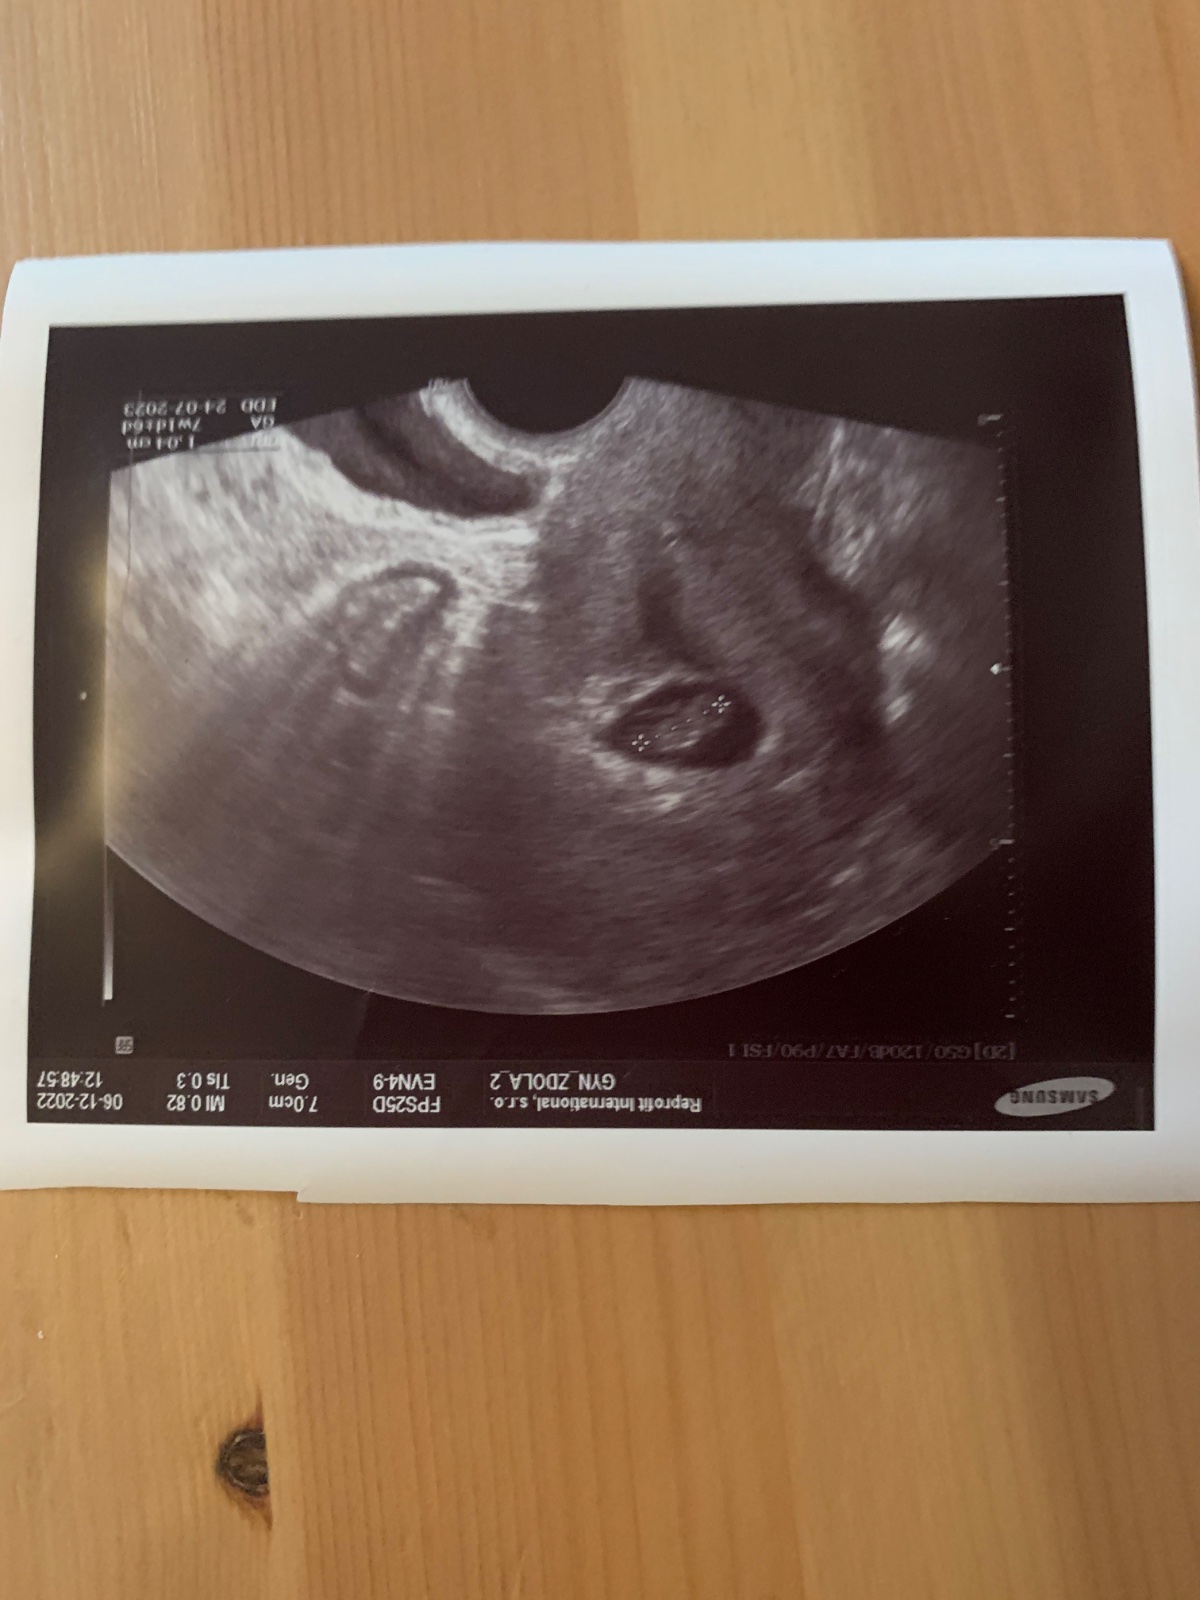

@berushe14 takže to naproti je ono?

Vypadá to jako kdyby tam bylo jedno ještě naproti ale prázdný

@kristynaprandl ano, to je syndrom mizejiciho dvojcete